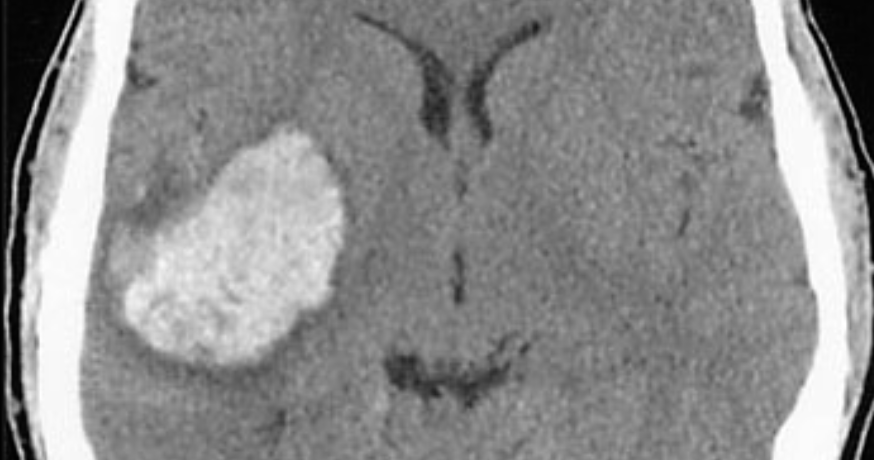

Case 6

Axial CT scan obtained in a 57-year-old man who presented with left hemiplegia and obtundation.

Axial CT scan obtained in a 57-year-old man who presented with left hemiplegia and obtundation.

Name the site of the lesion?

---basal ganglia---

What is commonest cause of this lesion?

---hypertension---